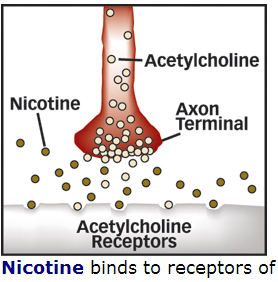

and the LINK to the bio-molecular communications molecule ……ace –> acetylcholine

Acetylcholine – Wikipedia, the free encyclopedia

https://en.wikipedia.org/wiki/Acetylcholine

Wikipedia

Acetylcholine is an organic chemical that functions in the brain and body of many types of animals, including humans, as a neurotransmitter—a chemical …

History · Function · Synthesis and degradation · Receptors

Acetylcholine Neurotransmission (Section 1, Chapter 11 …

neuroscience.uth.tmc.edu › Table of Contents

11.1 Introduction. Acetylcholine, the first neurotransmitter discovered, was originally described as “vagus stuff” by Otto Loewi because of its ability to mimic the …

Acetylcholine – Neuroscience – NCBI Bookshelf

www.ncbi.nlm.nih.gov › … › Bookshelf

National Center for Biotechnology Information

by D Purves – 2001

Acetylcholine is the neurotransmitter at neuromuscular junctions, at synapses in the ganglia of the visceral motor system, and at a variety of sites within the …

Choline transporter —> newspaper messages via –> Cho + line –> Mr. Cho an English major and Virginia tech and his line(s) …. choline messages

Acetylcholine – Wikipedia, the free encyclopedia

https://en.wikipedia.org/wiki/Acetylcholine

Wikipedia

Acetylcholine is an organic chemical that functions in the brain and body of many types of ….. The enzyme acetylcholinesterase converts acetylcholine into the inactive metabolites choline andacetate. This enzyme is abundant in the synaptic …

acetylcholinesterase converts acetylcholine into the inactive metabolites choline and acetate.